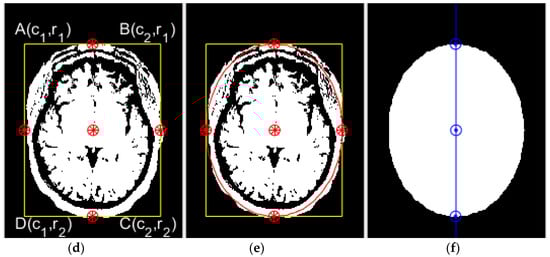

Figure 6.

Elliptical area extraction. (a) Input image, (b) binary image, (c) noise removal, (d) rectangular boundary extraction, (e) elliptical area extraction, and (f) symmetric axis (midline) extraction using PCA.

Now, the parameters of an ellipse can be determined as:

Now, within I(i, j), which consists of all the pixels inside the elliptical boundary, the pixels are set to “1” based on Equation (25), as shown in Figure 6e,f, respectively.